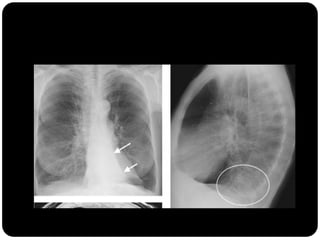

Em que lobo está essa lesão?

Resposta: LID

Importância do

perfil;

Importância da

ausência do sinal da

silhueta;